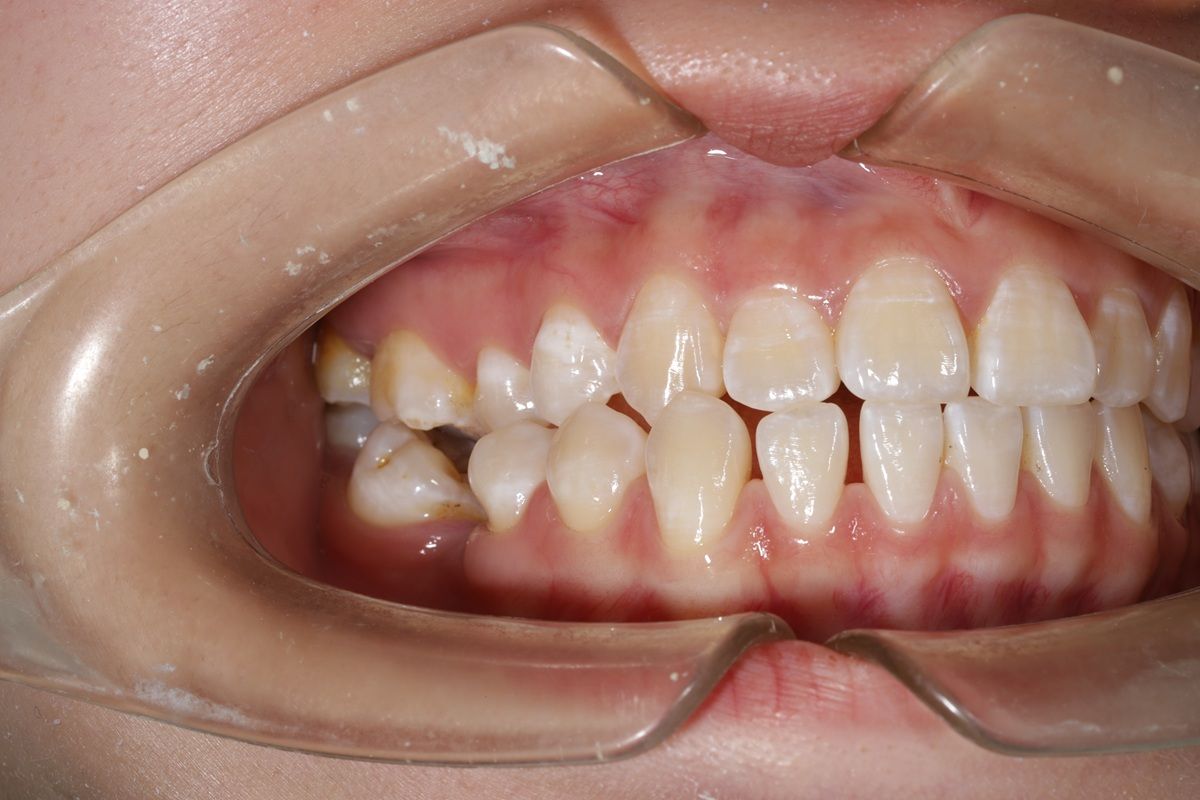

Tình trạng răng trước khi niềng

- Răng thưa, khoảng cách giữa các răng lớn gây mất thẩm mỹ.

- Răng khấp khểnh, lệch cung, thiếu sự cân đối tổng thể.

- Sai khớp cắn, ảnh hưởng chức năng ăn nhai và khiến gương mặt thiếu hài hòa.